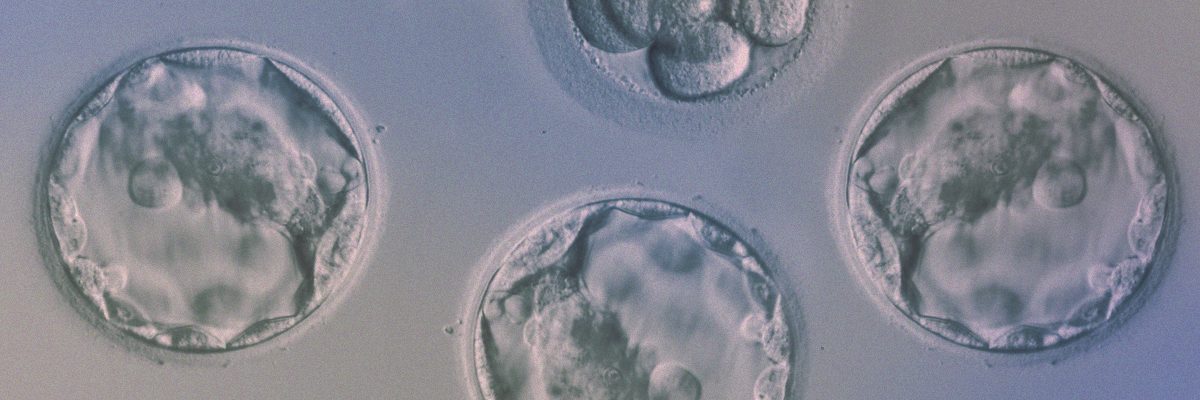

Фото Эмбриона На 5